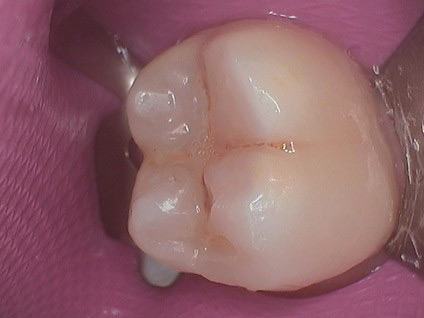

1. Canary Reading

2. Revealing Decay